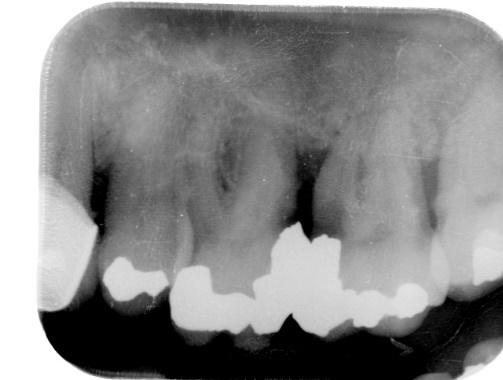

Lower Molar Primary root canal treatment